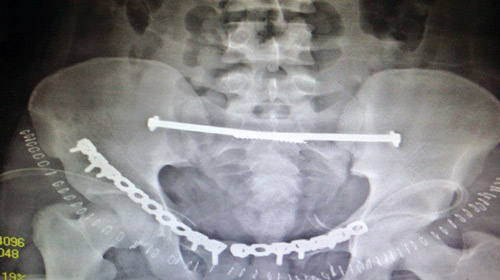

وبعد استقرار الحالة العامة للمريض، تمت مناظرة الكسور الموجودة من قبل الدكتور محمد فوزي رئيس قسم العظام، الذي قرر إجراء تدخل جراحي لفتح وتثبيت الكسور المتعددة في الحوض بواسطة شرائح ومسامير معينة.

وبالفعل تم عمل التحاليل اللازمة، ودخول المريض لغرفة العمليات، حيث تم فتح وتثبيت الكسور. وبحمد الله وتوفيقه تمت العمليات جميعها بالحوض في جلسة واحدة وبنجاح تام ومكث المريض في المستشفى عدة أيام بعد الجراحة للاطمئنان على الحالة العامة والغيار المستمر على الجروح. وبحمد الله خرج المريض من المستشفى بحالة جيدة واستمر في المتابعة بالعيادة الخارجية بقسم العظام في المستشفى حتى تمكن من المشي بصورة منتظمة وطبيعية.